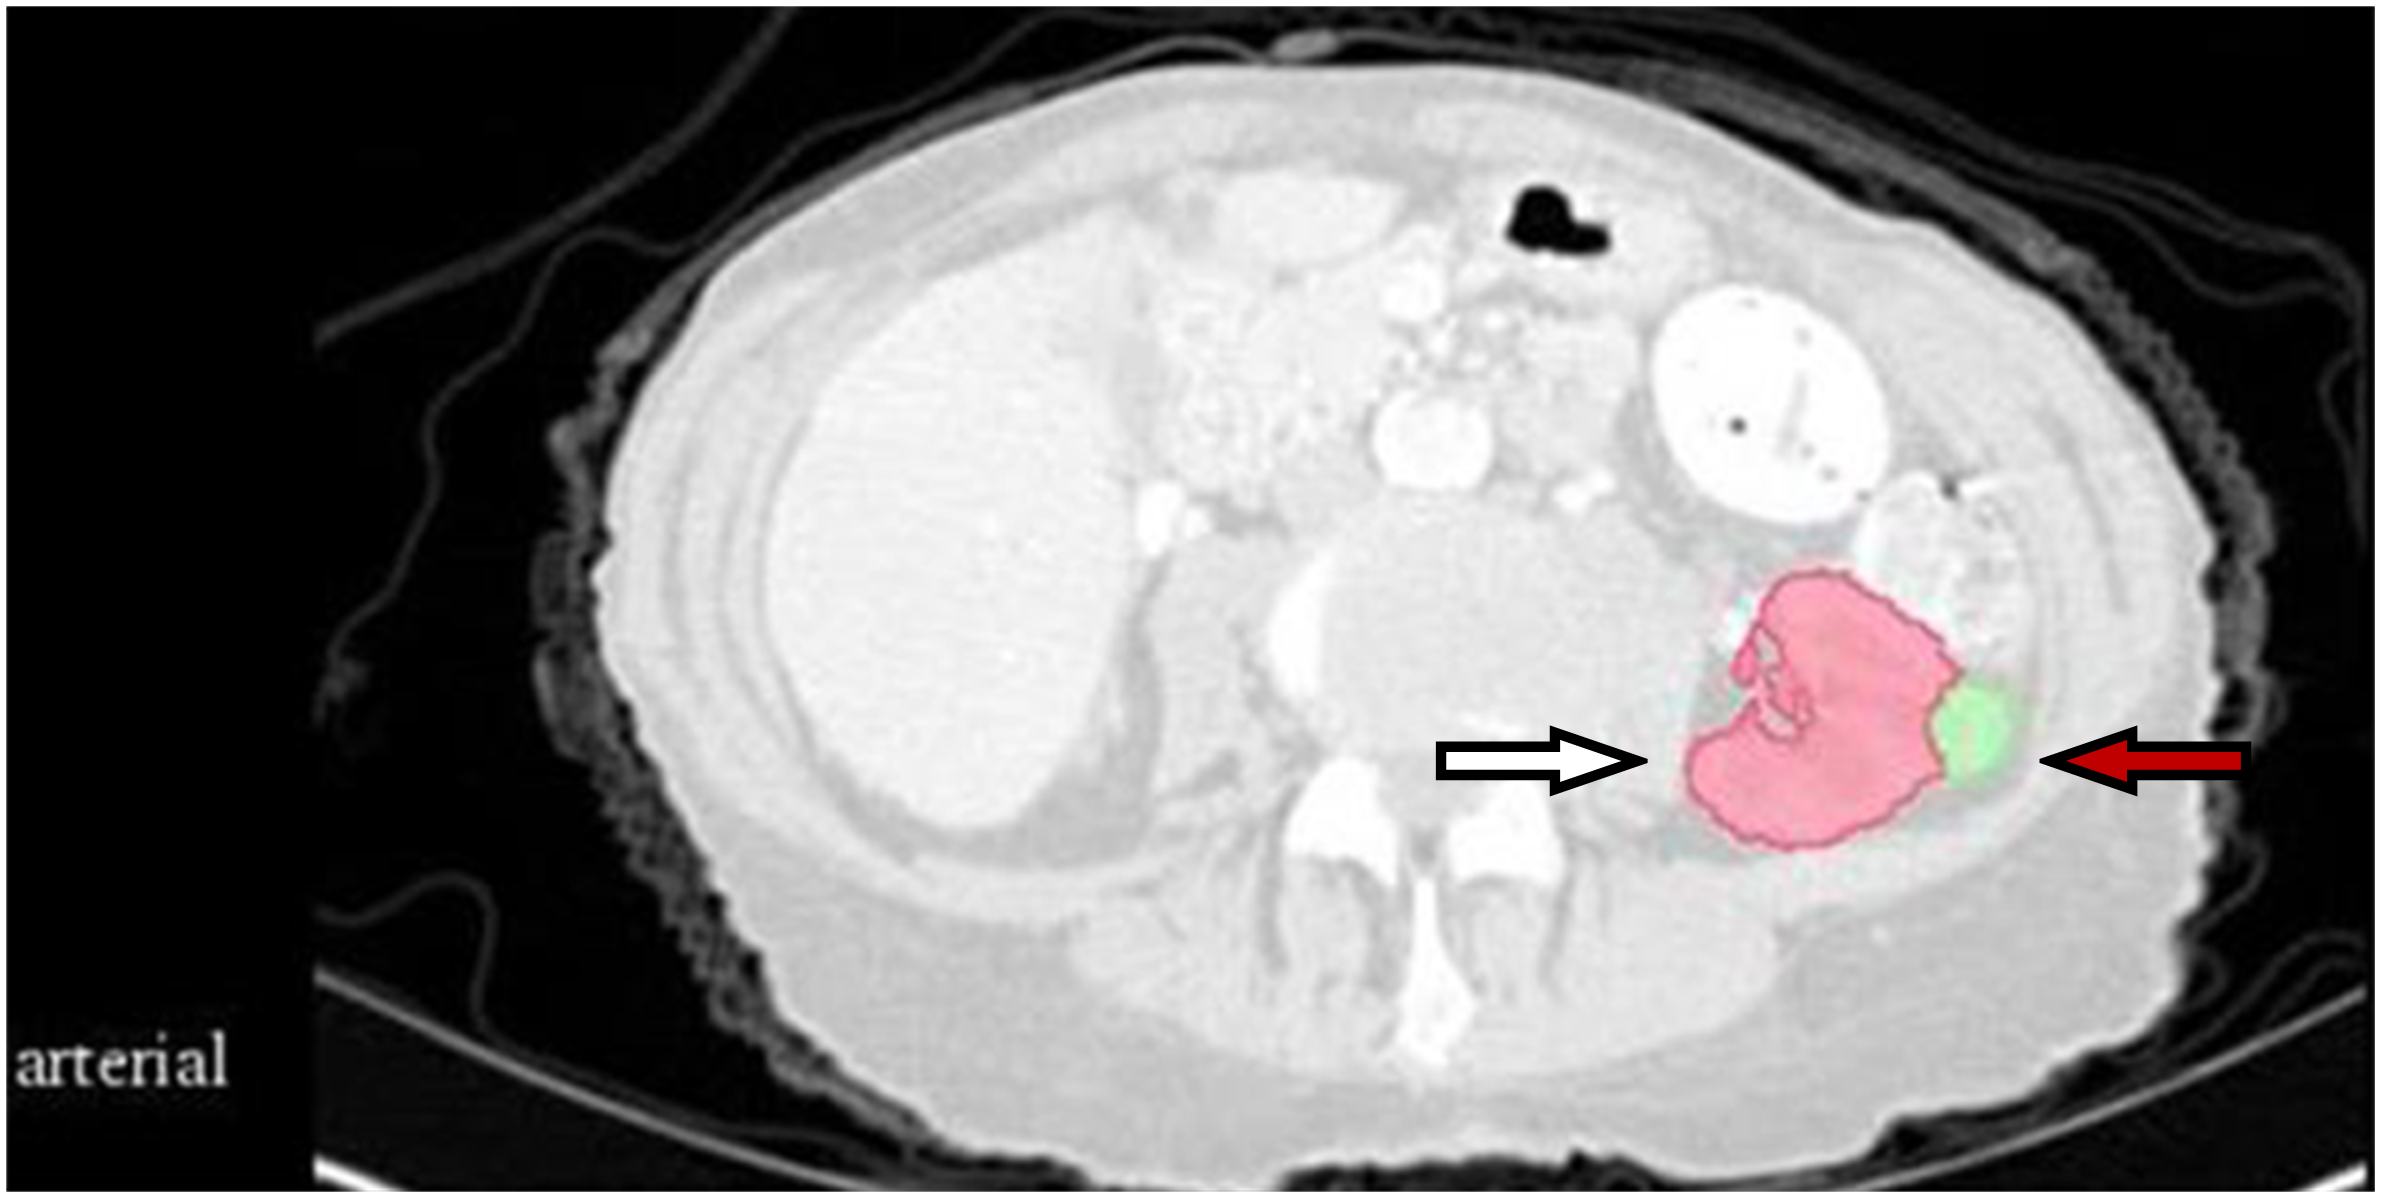

The CT images were preprocessed using wavelet-based methods. Before feature extraction, all images were resampled according to a voxel size of 1 × 1 × 1 mm3. The gross tumor volume (GTV) and normal kidney tissue were regarded as the regions of interest. Feature extraction was based on a three-dimensional (3D) slicer platform and performed using the pyradiomics package; the package is available at http://PyRadiomics.readthedocs.io/en/latest/ (last accessed on June 30, 2019). The eigenvalue data of all radiomic features were processed using z-score standardization. Figure 1 shows a CT sectional view of a patient in the training set. The CT radiomic feature variables of the GTV and normal kidney tissue were extracted. A total of 837 radiomics features were extracted, including first-order statistics, gray level co-occurrence matrix (GLCM), gray level dependence matrix (GLDM), gray level run length matrix (GLRLM), gray level size zone matrix (GLSZM), and neighboring gray tone difference matrix (NGTDM). Shape features were removed in this study. First-order features describes single pixel or voxel within the ROI. GLCM defines different combination of gray levels of an image area. GLDM quantifies the gray level dependencies in an image. GLRLM provides information about runs of consecutive pixels with the same gray level. GLSZM quantifies gray level zones in an image. And wavelet-based features were transformed based on above features.

Figure 1

CT section of one patient in the training set. The white arrow indicates normal kidney tissue, and the red arrow indicates gross tumor volume.